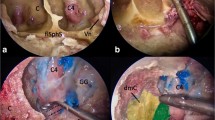

At this stage, intradural exploration was further advanced in a superior direction after ligation of the superior petrosal sinus, followed by elevation and cutting of the tentorium. Subsequently, the middle tentorial incisura space was evaluated via the ventral endoscopic transorbital pathway. This space was explored from the origin of the oculomotor nerve to the entrance of the trochlear nerve into the tentorium free edge. The anterolateral portion of the mesencephalon was visualized at the center of the surgical field, surrounded by the superior cerebellar artery as it coursed over the trigeminal pore. Continuing with the dissection medially, the oculomotor nerve was identified at its cisternal segment, arising from the ponto-mesencephalic sulcus. More laterally, the trochlear nerve was recognized in the ambiens division of its cisternal segment, as it emerged from the dorsal brainstem and turned around the mesencephalon in close relation with the superior cerebellar artery and the free edge of the tentorium (Fig. 11).

The posterior fossa neurovascular structures belonging to the middle tentorial incisura space can be showed after elevating the tentorium (a, b). The mesencephalic portion of the brainstem can be appreciated (c) as well as the origin of the fourth and third cranial nerve (d). T tentorium, V trigeminal nerve, III third cranial nerve, IV trochlear nerve, M mesencephalic portion of the brainstem, sca superior cerebellar artery, MC Meckel’s cave, PA petrous apex

Ventral brainstem space

This most medial space was hardly accessible through the straight, ventral endoscopic transorbital trajectory. However, only by means of a 30° lens, the abducens nerve was appreciated as it entered the cavernous sinus from Dorello’s canal. Additionally, the basilar trunk at the midline gives origin to the anterior-inferior cerebellar artery (Fig. 12).

The ventral brainstem area can be showed via the transorbital approach. The abducens nerve can be seen in the cavernous sinus (a) entering from the Dorello’s canal (b, 30° angle endoscope turned medially). The anterior-inferior cerebellar artery coming from the basilar artery trunk can be appreciated by means of a 30° endoscope (c). csICA cavernous internal carotid artery, VI abducens nerve, V trigeminal nerve, GG gasserian ganglion, BA basilar artery, aica anterior-inferior cerebellar artery, Cl clivus, Pons pons portion of the brainstem, PSL petrosphenoid ligament. *Dorello’s canal